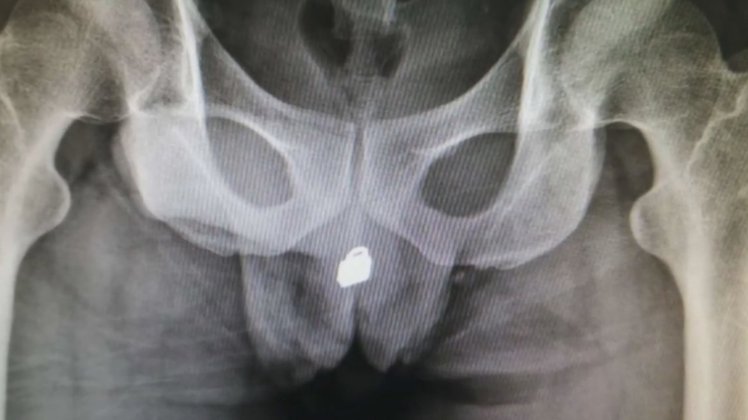

However, the padlock went up into his bladder and it became stuck there. Try as he may, he couldn’t get it out so he was taken to hospital in Fuzhou city in east China and shocking X-rays showed the padlock jammed into his organ.